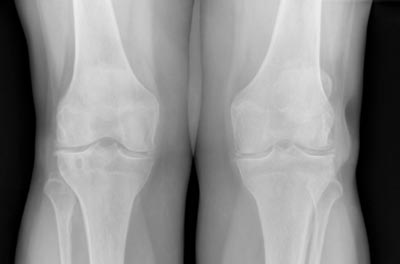

Arthrosebehandlung

Die Arthrose ist ein Verschleiß des Gelenkknorpels. Sie entwickelt sich normalerweise in der zweiten Lebenshälfte. Besonders häufig sind die Hüft- und Kniegelenke betroffen. Durch die verschlechterte Gleitfähigkeit der Gelenkpartner entstehen Schmerzen.